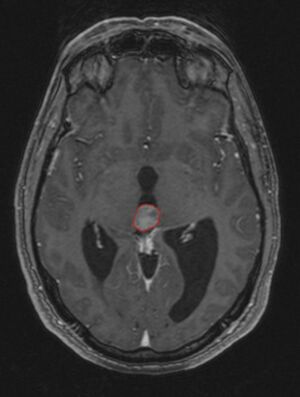

في كثير من الأحيان ، يُعرف شلل الحملقة إالعلوي جنبًا إلى جنب مع العديد من الموجودات العينية مثل رأرأة تراجع التقارب وتراجع الجفن المعروف أيضًا باسم علامة كولير وانفصال الضوء القريب (تتكيف الحدقة مع الضوء ولكنها لا تتفاعل مع الضوء) يسموا كمجموعة بمتلازمة بارينو[1] أو متلازمة الدماغ المتوسط الظهرية ، هي الأعراض الجسدية الوحيدة التي تظهر. يحدث هذا بسبب ضغط مركز الحملقة العمودي في سقف الدماغ المتوسط على مستوى الأكيمة العلوية والعصب القحفي III. يتضمن العمل عادةً التصوير العصبي كما يظهر على اليمين.[citation needed]